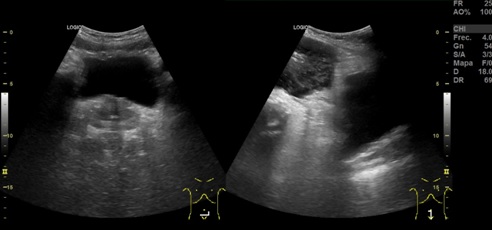

Hallazgos ecográficos: en región umbilical se aprecia una neoformación de contenido heterogéneo de unos 15 cm de diámetro. Imágenes compatibles con Esteatosis hepática. Quistes renales derechos. Esplenomegali.